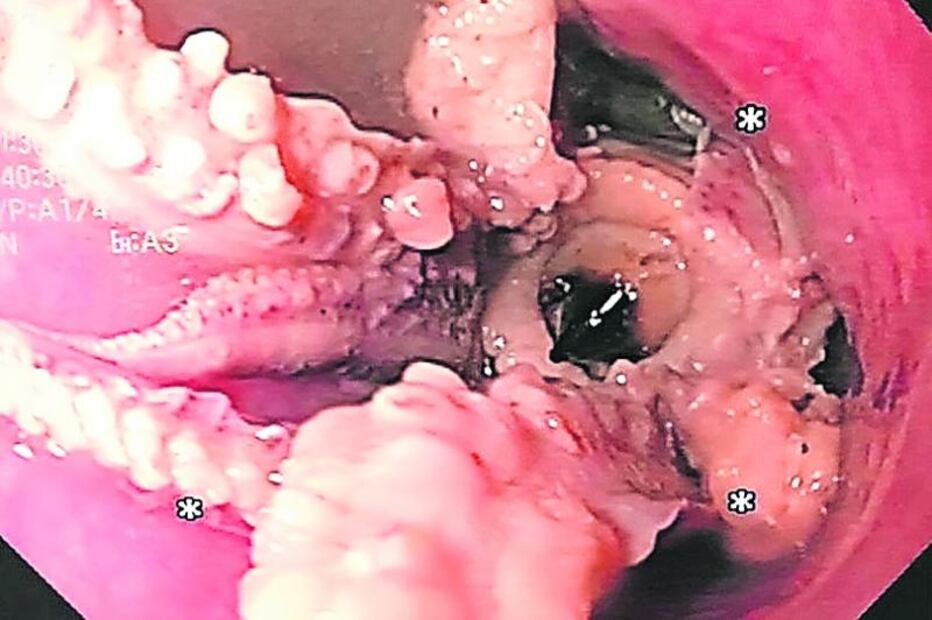

Al hombre se le realizó una esófagogastroduodenoscopia, la cual dejaba ver al pulpo completo con sus ventosas pegadas a 5 cm de la unión gastroesofágica. Sin embargo, los intentos iniciales del equipo médico de extraer a la criatura no tuvieron éxito. Finalmente, se maniobró cuidadosamente el endoscopio más allá de la masa, hasta el estómago.

Luego, los médicos utilizaron fórceps para agarrar la cabeza del pulpo y extraerla. El paciente se recuperó rápidamente del procedimiento y fue dado de alta dos días después. Los médicos dijeron que los bloqueos de alimentos son uno de los problemas más comunes que encuentran en su trabajo en el hospital. Recientemente, extrajeron un teléfono celular.